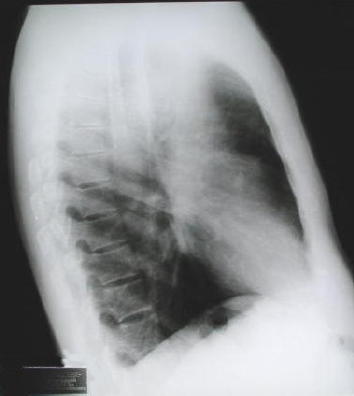

Rx. control

pos - operatorio

Rx. pos - operatoria

inmediata.

a. observe

la expansión pulmonar del lado izquierdo.

b. la

traquea intubada y el mediastino se encuentran centrados en el tórax.

c. dos

tubos torácicos fueron utilizados para drenaje y expansión

pulmonar.

Nota: las imágenes

redondeadas corresponden a electrodos electrocardiográficos.